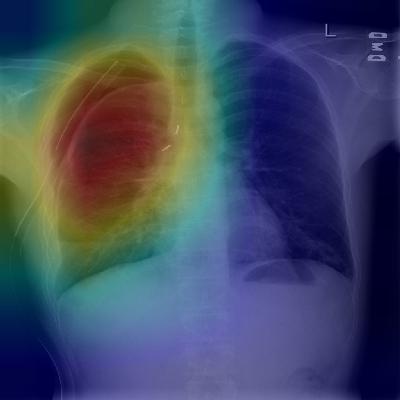

Figure 1: CheXNet is a 121-layer convolutional neural network that takes a chest X-ray image as input, and outputs the probability of a pathology. On this example, CheXnet correctly detects pneumonia and also localizes areas in the image most indicative of the pathology.

Our model, ChexNet (shown in Figure 1), is a 121-layer convolutional neural network that inputs a chest X-ray image and outputs the probability of pneumonia along with a heatmap localizing the areas of the image most indicative of pneumonia. We train CheXNet on the recently released ChestX-ray14 dataset (Wang et al., 2017), which contains 112,120 frontal-view chest X-ray images individually labeled with up to 14 different thoracic diseases, including pneumonia. We use dense connections (Huang et al., 2016) and batch normalization (Ioffe & Szegedy, 2015) to make the optimization of such a deep network tractable.